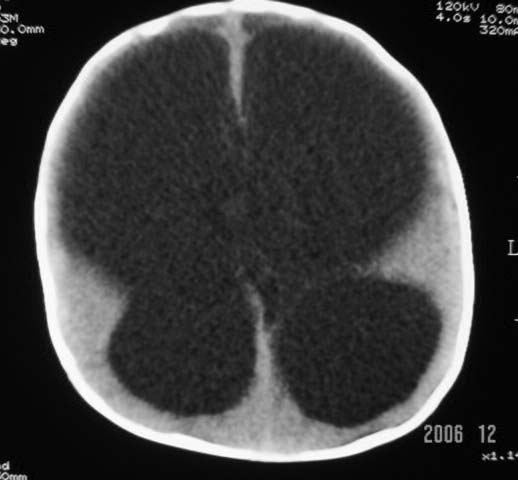

3m,出生时有新生儿吸入性肺炎、hie、化脓性脑膜炎,近一个月发现头围增大(51cm),无恶心呕吐。

第四脑室有增大,应该是交通性脑积水

3m,出生时有新生儿吸入性肺炎、hie、化脓性脑膜炎,近一个月发现头围增大(51cm),无恶心呕吐,脑室系统全程扩张,脑皮质变薄,结合病史考虑交通性脑积水

脑室全部扩大结合化脓性脑膜炎病史考虑重度交通性脑积水.

3m,出生时有新生儿吸入性肺炎、hie、化脓性脑膜炎,近一个月发现头围增大(51cm),无恶心呕吐,脑室系统全程扩张,脑皮质变薄,结合病史考虑重度交通性脑积水。